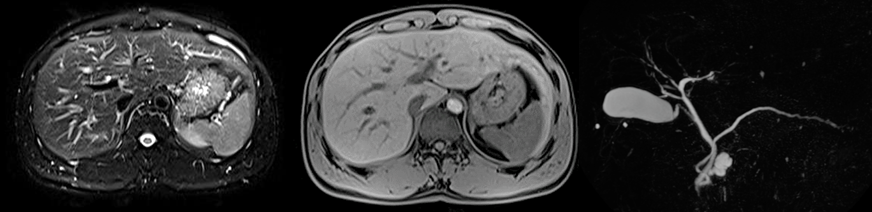

上腹部MRI+MRCP(造影なし)

肝臓、膵臓(膵管)、胆嚢(胆管)など上腹部臓器の結石や嚢胞性病変、がんの検出などに優れています。内視鏡と比較して負担や苦痛、合併症の少ない検査です。家族歴のある方や飲酒の多い方、肝機能異常の指摘がある方などにお勧めしています。ドックでは原則造影剤を使用しないで撮影しますが、より鮮明な画像撮影をご希望される方は追加料金2,200円で経口造影剤(ボースデル)を使用して撮影することも可能です。